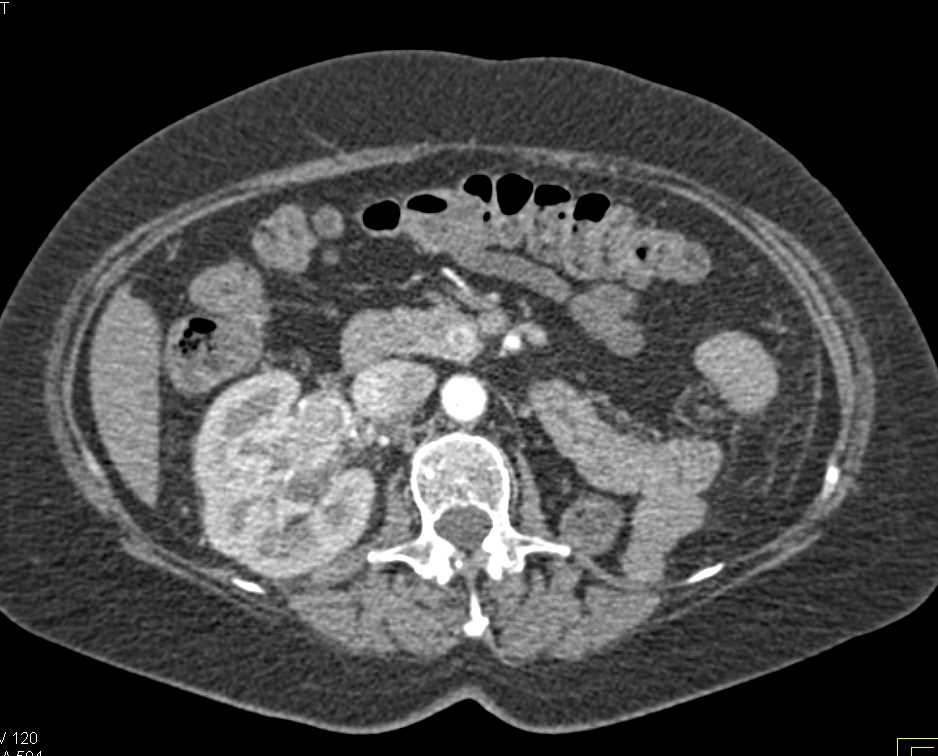

3D Mapping of Normal Vasculature and Minimal Plaque